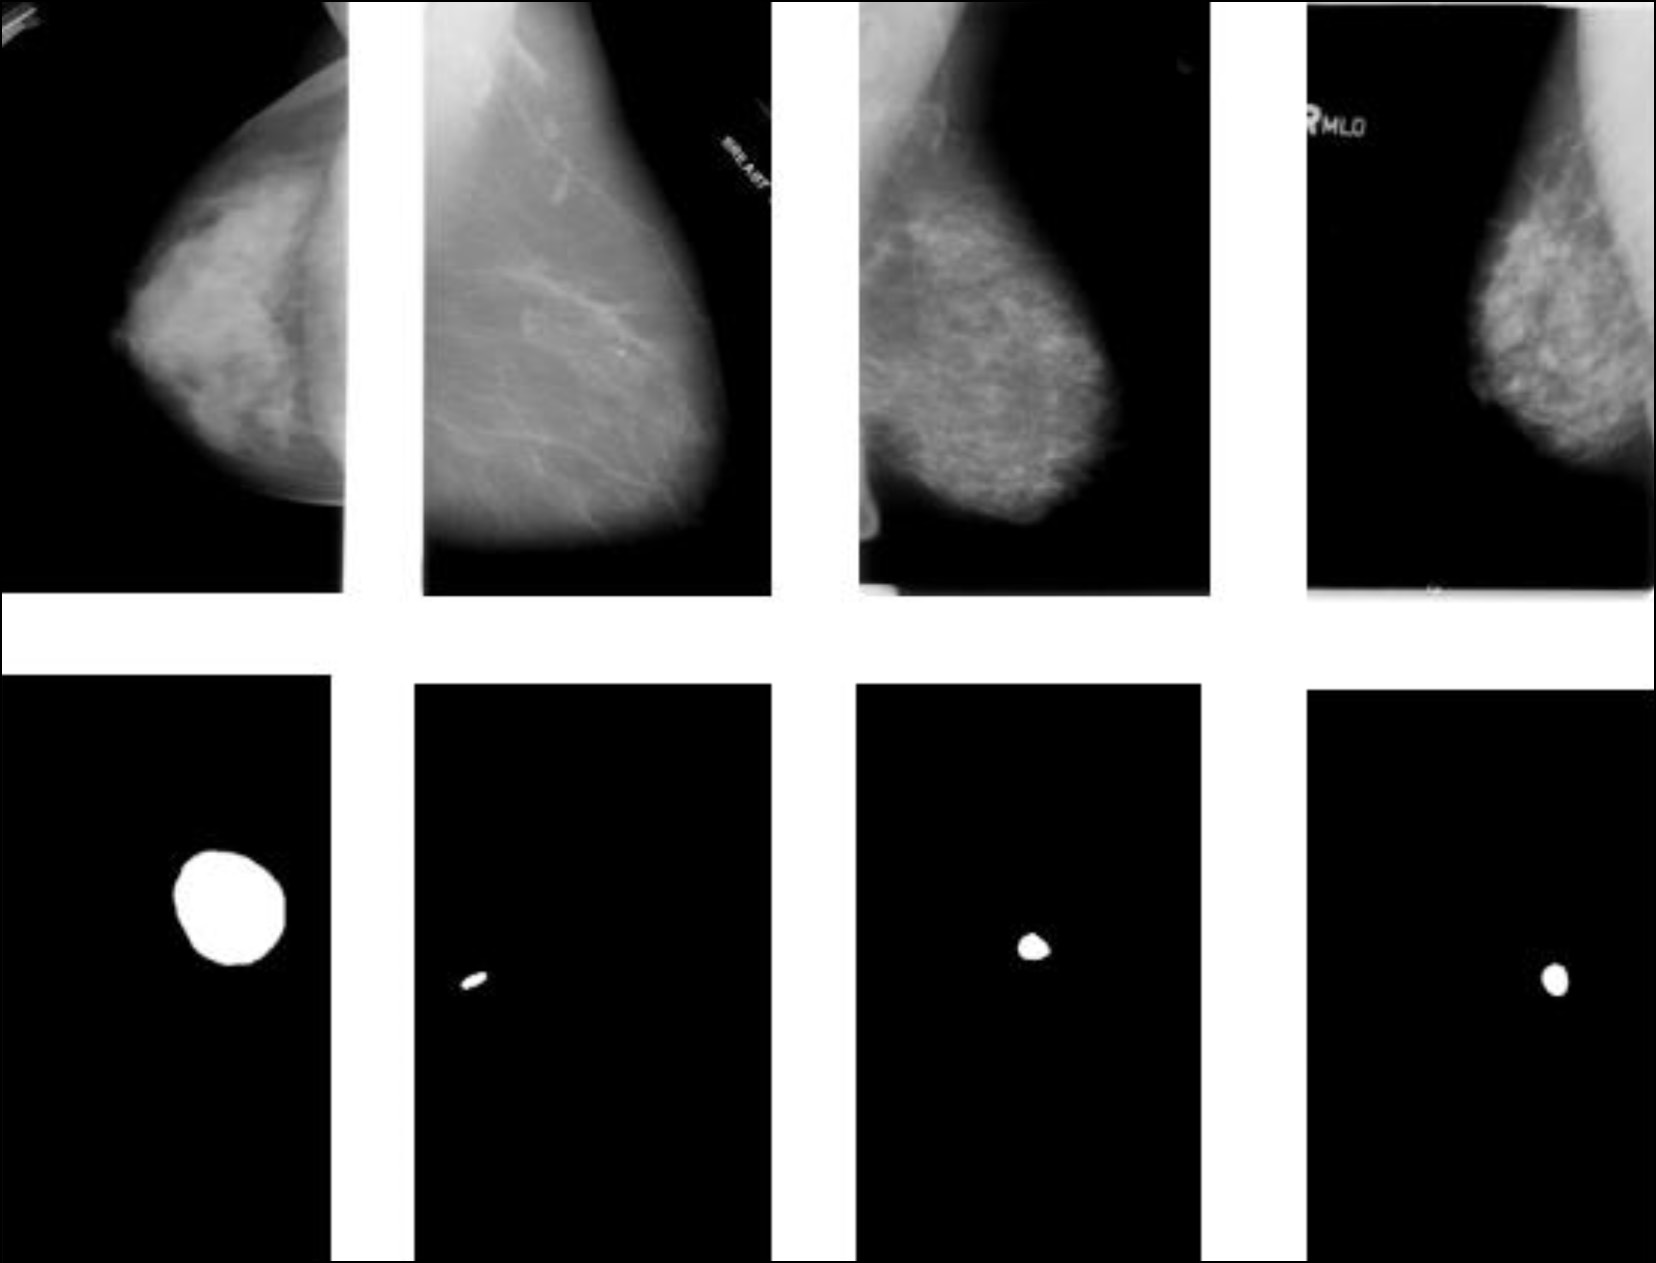

В другом исследовании применялась свёрточная ИНС для локализации опухоли, даже если она развилась в нескольких областях, а также для классификации опухоли на доброкачественную или злокачественную [3]. Пример работы данной модели представлен на рис. 1. Полученный классификатор показал точность в тестовых примерах около 85%, что может быть использовано в качестве вспомогательного инструмента для радиолога при выявлении рака молочной железы.

Рис. 1. Пример локализации опухоли [3].